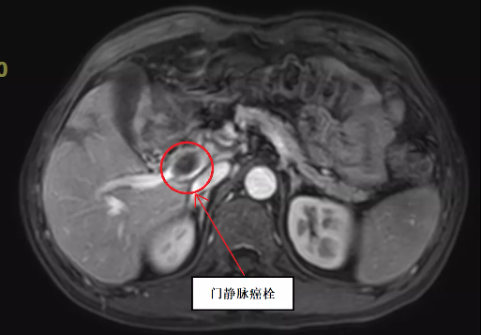

据肝胆·介入科徐耀端主任介绍,患者李某某,男性,56岁,石屏人,在3个多月前发现肝脏占位,其间,辗转云南省内多家三甲医院均被认为不能通过手术切除肝脏肿瘤及癌栓。而后,患者经过多方打听,于2021年11月16日到红河州第三人民医院肝胆·介入科就诊。患者入院后给予完善3.0 T核磁共振及320排CT等相关检查,经过该院肝胆·介入科、肿瘤内科、放射科、放疗科等9个科室专家参与的专病多学科会诊(MDT)讨论,研究制定详细手术方案,并于2021年11月23日在红河州第三人民医院肝胆·介入科行“左半肝切除+尾状叶切除+门静脉切开取栓术”,手术过程顺利,术后患者恢复情况良好,于2021年12月1日顺利康复出院。